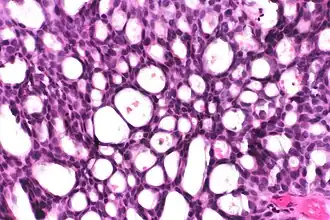

This can be done to slides processed by the chemical fixation or frozen section slides. To see the tissue under a microscope, the sections are stained with one or more pigments. The aim of staining is to reveal cellular components; counterstains are used to provide contrast.

The most commonly used stain in histology is a combination of hematoxylin and eosin (often abbreviated H&E). Hematoxylin is used to stain nuclei blue, while eosin stains the cytoplasm and the extracellular connective tissue matrix of most cells pink. There are hundreds of various other techniques which have been used to selectively stain cells. Other compounds used to color tissue sections include safranin, Oil Red O, congo red, silver salts and artificial dyes. Histochemistry refers to the science of using chemical reactions between laboratory chemicals and components within tissue. A commonly performed histochemical technique is the Perls' Prussian blue reaction, used to demonstrate iron deposits in diseases like Hemochromatosis.[2]

Cribriform: Solid with multiple clear spaces. -